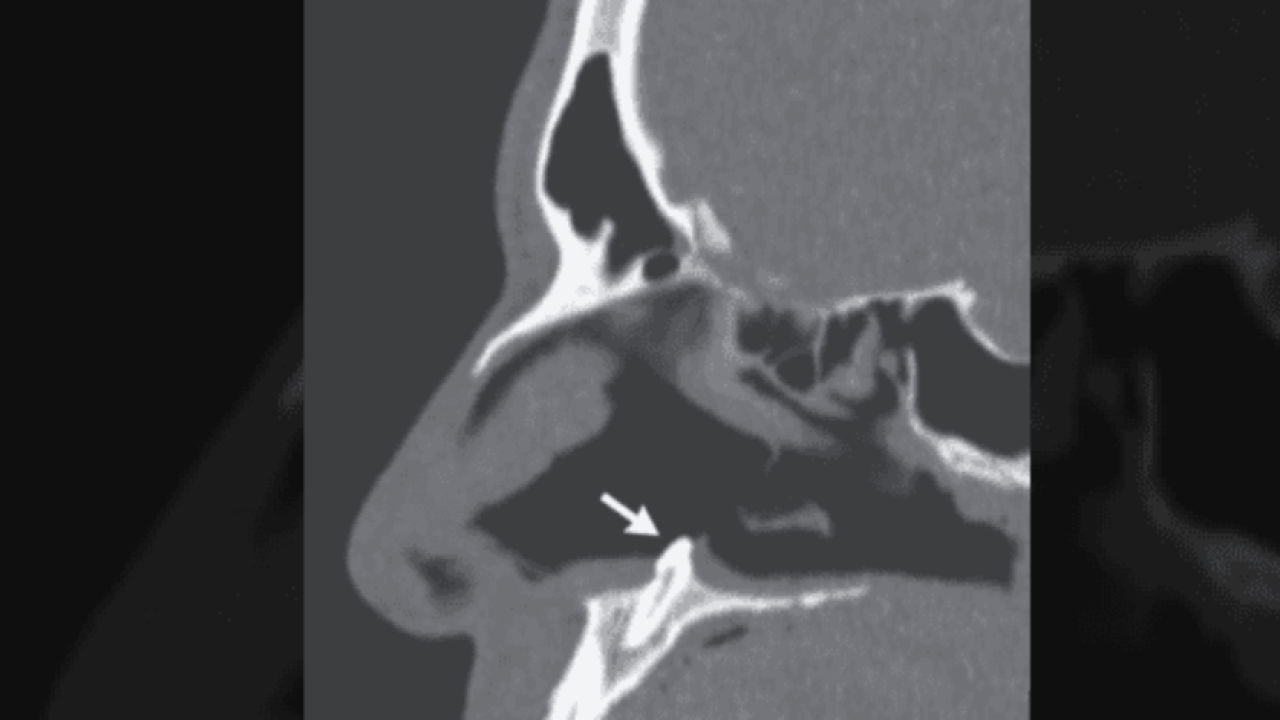

Amerika Birleşik Devletleri'nin New York eyaletinde meydana gelen olay, tıp literatürüne girdi. Uzun süredir burun tıkanıklığı şikayeti yaşayan adam, durumu dayanılmaz hal alınca doktora gitti. Doktorlar, yaptıkları ilk muayenenin ardından adamın burnunda daha önce karşılaşmadıkları bir manzara gördü. Çünkü adamın burnundaki tıkanıklığa neden olan şey, orada olmaması gereken dişti.

Doktorlar, karşılaştıkları bu ilginç durumun ardından ne yapacaklarına karar vermek için acil olarak toplantı kararı aldı. Yapılan görüşmeler ve tetkikler sonucunda adamın hemen ameliyata alınması kararlaştırıldı. New York'taki Mount Sinai Hastanesi'nde gerçekleştirilen ameliyatın ardından 38 yaşındaki adamın burnundaki diş, başarılı şekilde çıkarıldı.

Tıp dünyasında daha önce eşine çok az rastlandığı belirtilen olay, New England Tıp Dergisi'nde de yayınlandı. Dergideki yazıda, "Hasta bir kaç yıldan bu yana burun tıkanıklığı yaşadığını belirtti ancak daha önce yüz travması ya da başka bir anormallikle karşılaşmadığını anlattı. İlk muayenenin ardından buruna takılan kamera sayesinde, burunda olmaması gereken bir diş parçası tespit edildi. Bu parça başarılı ameliyat sonucu alındı" ifadelerine yer verildi.